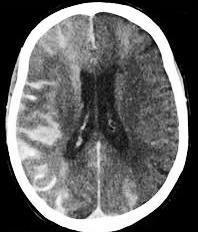

Hemorragia Subaracnóide (HSA)

O que mostra a TC?

Lesão hiperdensa (branca),

logo no início dos sintomas.

Exames diagnósticos?

TC sem contraste: “mickey”;